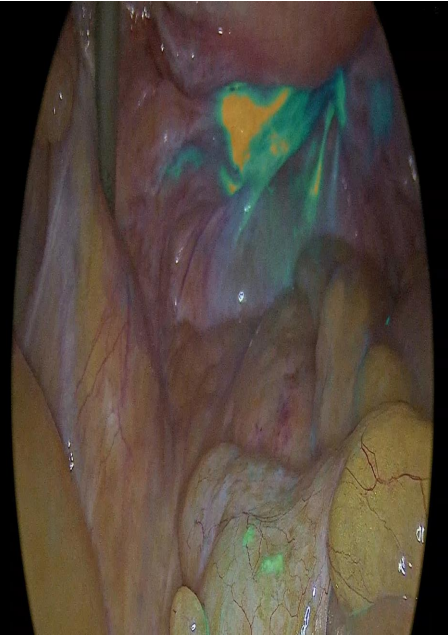

Figure 4: Sentinel node depiction after ICG application.Laparoscopic sentinel node mapping complicating endometrial cancer. Report of three cases and systematic review of the literature. Sofoudis C, Syrios K, Oikonomidis M, Betas P, Zioris K. Obstet Gynecol Int J 2022;13(2):135-138